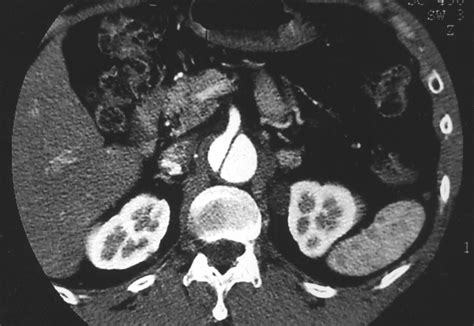

• Cancer Detection: Spiral CT Scans are instrumental in detecting and staging cancer, particularly in the lungs, liver, and other organs. The detailed images help in identifying tumors and assessing their size and location.

• Gastrointestinal Imaging: Spiral CT Scans help in diagnosing conditions such as appendicitis, diverticulitis, and inflammatory bowel disease by providing clear images of the digestive tract.

Interpreting Spiral CT Scan results requires specialized training and expertise. The radiologist will look for signs of disease, injury, or other conditions based on the detailed images provided by the scan.